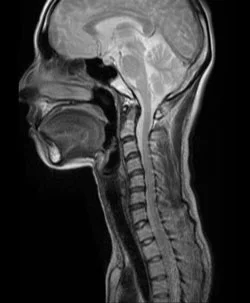

脳脊髄が減少して頭痛や目の眩しさ、耳鳴りが起こることは以前から知られていたのですが、原因はあまり知られていませんでした。私達は以前から、腰椎穿刺やむち打ちが原因の頭痛や不定愁訴の鍼治療に取り組んできました。ブラッドパッチの後遺症の治療に効果的なので、早めに鍼治療をしましょう。

詳しくは、 脳脊髄液減少症・濾出症・低髄液圧症候群に鍼治療は効果があるか?をご覧ください。